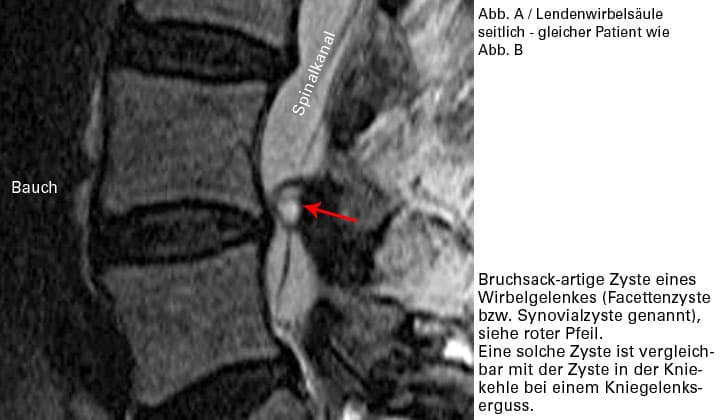

Überlastungsreizungen können in den Wirbelgelenken einen Reizerguss auslösen. In seltenen Fällen kann dieser Reizerguss bewirken, dass sich die Gelenkschleimhaut wie ein Bruchsack durch die Gelenkskapsel vorstülpt und eine Synovialcyste bildet. Diese kann eine Nervenwurzel quetschen und muss u. U. operiert werden.